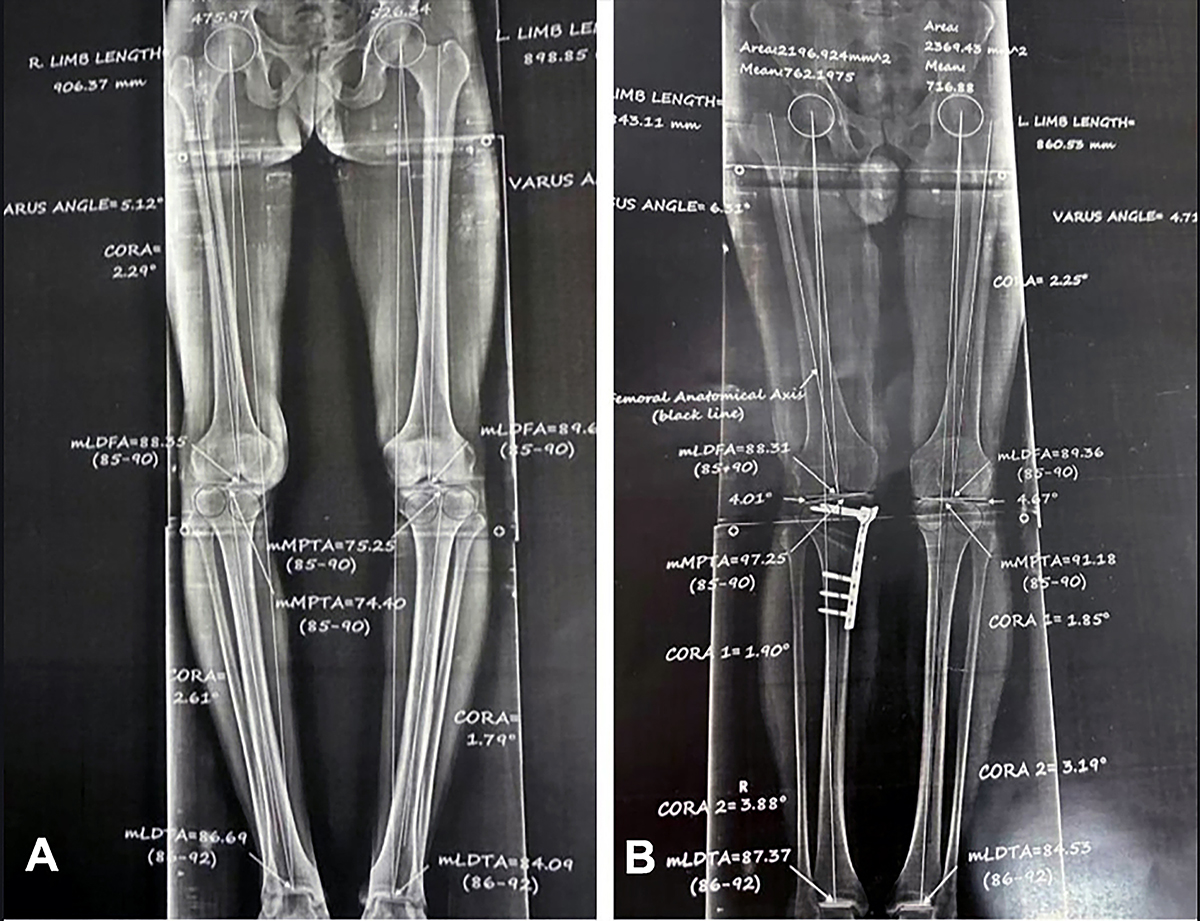

A standing whole lower limb radiograph (A) preoperative and (B) 3 months postoperative.